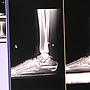

[心得] 扁平足矯正術後復健心得

[ MuscleBeach ]

16

留言, 推噓總分:

+16

作者: yusan30919 - 發表於

2019/12/07 22:26

(6年前)

[心得] 扁平足開刀手術過程心得分享

86

+65

2019/09/30 17:36